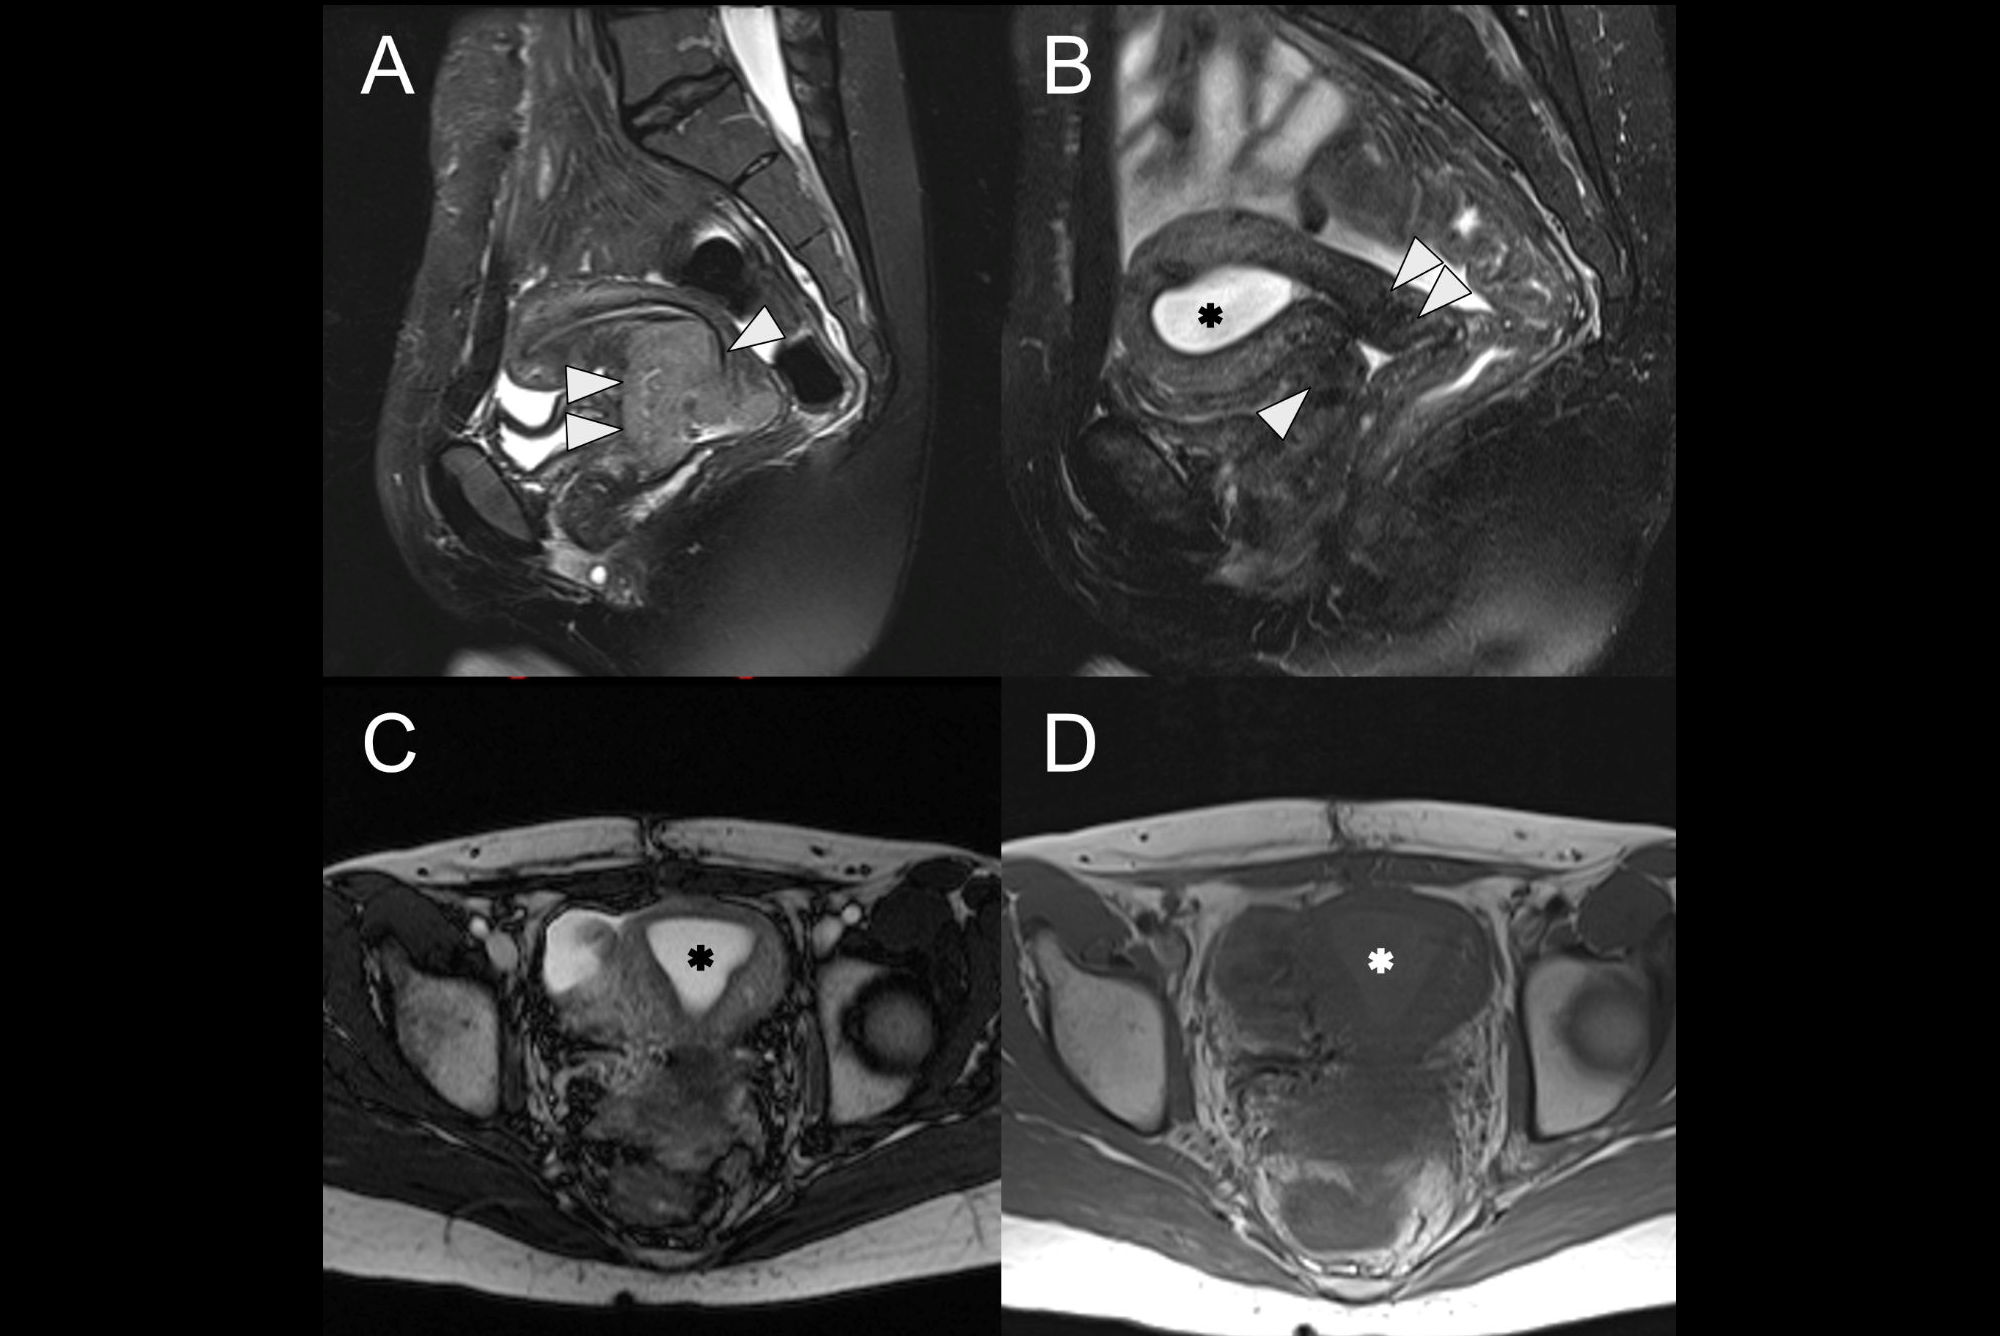

CT coronal; 25-year-old woman -- a large cystic mass in the anterior mid pelvis with smooth hyperdense borders. It converges to the right at a focal area of vascular twisting (whirlpool sign).All figures courtesy of the Medical Imaging Department, Mackay Base Hospital, Mackay, QLD, Australia, and the RANZCR 2025 annual scientific meeting.

In both cases presented in the poster, the diagnosis of ovarian torsion was made using CT; this diagnosis was confirmed with timely surgical intervention for both patients. While the patients’ symptoms varied, both involved nonspecific clinical findings with persistent pain, which led to contrast-enhanced CT exams of the abdomen and pelvis.

One patient, a 25-year-old woman, presented with right-sided tenderness and pain with nausea and vomiting over two days. She was afebrile, hemodynamically stable, and her lab markers were within normal ranges. The other patient, a 37-year-old woman, was also hemodynamically stable and afebrile; her tenderness and pain were left-sided and had persisted for four days.

CT sagittal; 25-year-old woman -- the cystic mass is causing mass effect on the urinary bladder and uterus. The left ovary is displaced posteriorly behind the mass (not imaged on this slice).

In the first case presented, CT showed a large right-sided adnexal cystic mass with evidence of a twisted vascular pedicle referred to as the “whirlpool sign,” suggestive of ovarian torsion. CT in the second case also showed a large lesion, which appeared to originate from a left-sided pedicle.

CT coronal; 37-year-old woman -- a large cystic mass in the anterior mid pelvis with smooth hyperdense borders. It converges to the right at a focal area of vascular twisting (whirlpool sign).